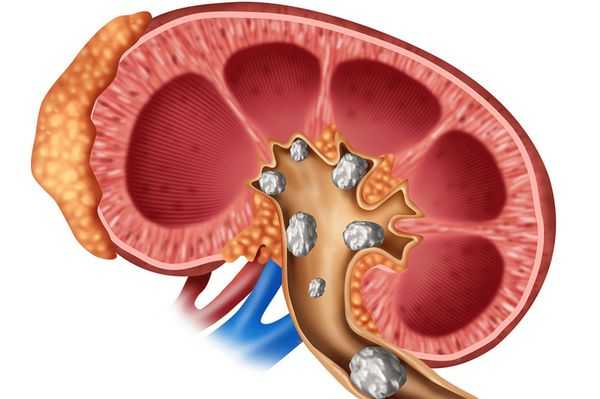

- почечную - с преобладанием мочекаменной болезни тяжелого течения, с частыми приступами почечной колики, развитием почечной недостаточности;

Гиперпаратиреоз проявляется избытком паратгормона, который способствует выведению из костной ткани кальция и фосфора. Кости становятся непрочными, размягчаются, могут искривляться, повышается риск возникновения переломов. Гиперкальциемия (избыточный уровень Ca в крови) приводит к развитию мышечной слабости, выделению избытка Ca с мочой. Усиливается мочеиспускание, появляется постоянная жажда, развивается почечнокаменная болезнь (нефролитиаз), отложение солей кальция в паренхиме почек (нефрокальциноз). Артериальная гипертензия при гиперпаратиреозе обусловлена действием избытка Ca на тонус кровеносных сосудов.

Висцеропатический гиперпаратиреоз характеризуется неспецифической симптоматикой и постепенным началом. При развитии гиперпаратиреоза возникает тошнота, желудочные боли, рвота, метеоризм, нарушается аппетит, резко снижается вес. У пациентов обнаруживаются пептические язвы с кровотечениями различной локализации, склонные к частым обострениям, рецидивам, а также признаки поражения желчного пузыря и поджелудочной железы. Развивается полиурия, плотность мочи уменьшается, появляется неутолимая жажда. На поздних стадиях выявляется нефрокальциноз, разиваются симптомы почечной недостаточности, прогрессирующей со временем, уремия.

Рентгенография позволяет обнаружить остеопороз, кистозные изменения костей, патологические переломы. Для оценки плотности костной ткани проводится денситометрия. При помощи рентгенологического исследования с контрастным веществом диагностируют возникающие при гиперпаратиреозе пептические язвы в желудочно-кишечном тракте. КТ почек и мочевыводящих путей выявляет камни. Рентгенотомография загрудинного пространства с пищеводным контрастированием бариевой взвесью позволяет выявить паратиреоаденому и ее местоположнение. Магнитно–резонансная томография по информативности превосходит КТ и УЗИ, визуализирует любую локализацию околощитовидных желез.